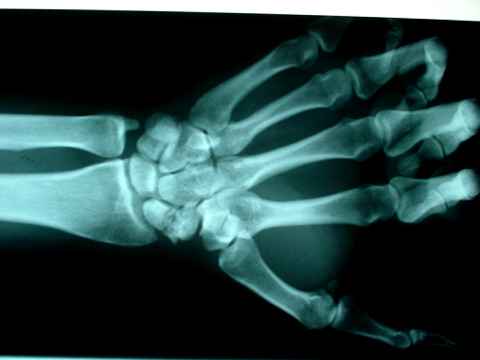

Y nos llevamos una sorpresa nada ver la placa...

El hueso escafoides está partido por la mitad y además tiene zonas de necrosis ósea e incluso una excrescencia ósea tipo espinoso en el fragmento distal.

Esto quería decir que este señor tuvo una fractura antigua. Que según la anamnesis se produjo hace tres años y desde entonces viene toreando y reiteradamente volviendo a partirse en dos el hueso; si es que alguna vez se soldó.

Lesión típica de los picadores. Hueso que ya no puede soldar y sólo nos queda el recurso de intervenir si las molestias lo ameritan y colocar algún tipo de fijación.

Detalle radiológico.